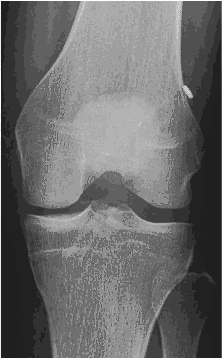

Le ligament croisé antérieur (LCA) est un ligament qui se situe au centre du genou. Son rôle est de stabiliser le genou. Il joue un rôle très important dans les sports de pivot (football, hockey, basket, rugby,etc). Sans ligament, il existe de réels risques d’entorses à répétition lors de la pratique sportive. Ces entorses entrainent à terme des lésions des ménisques et du cartilage favorisant le développement de l’arthrose à terme. Par sa vascularisation particulière et son anatomie, une fois rompu, il ne guérit pas spontanément.

Le diagnostique se fait par l’examen clinique et à l’aide d’une résonance magnétique.